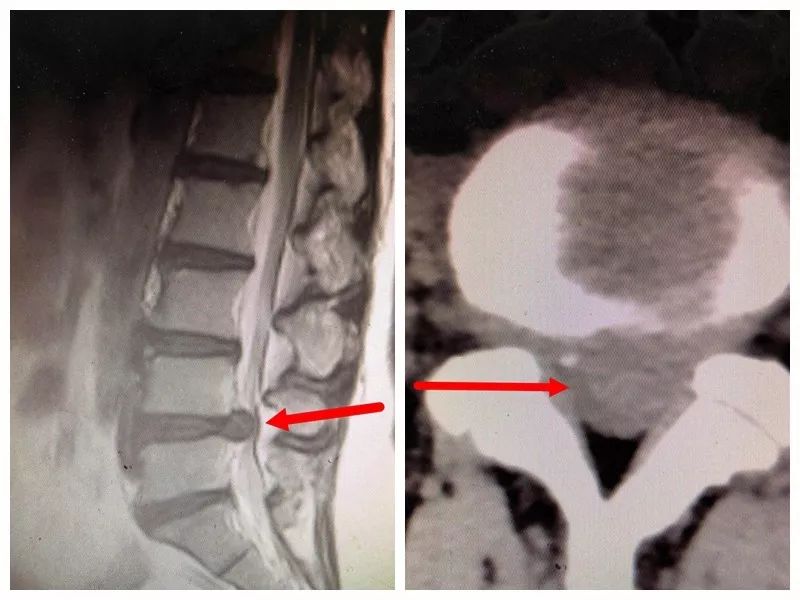

经当地医院检查,陈女士是患了腰间盘突出症,巨大椎间盘占椎管容积的五分之四,需要进行手术治疗。然而,当陈女士得知手术不仅需要全麻,还要在自己背部切开一个大切口进行,术后还需要长期卧床休息时,陈女士胆怯了。